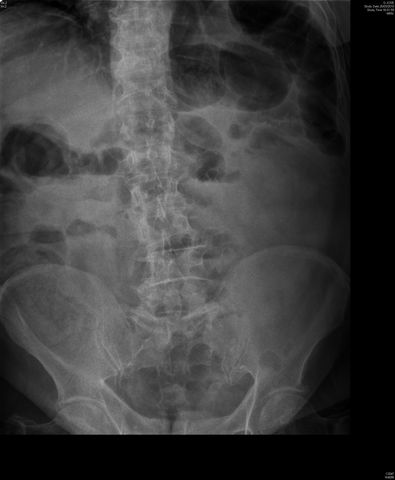

Diverticulosis de colon.

Diverticulosis de colon. Megacolon.